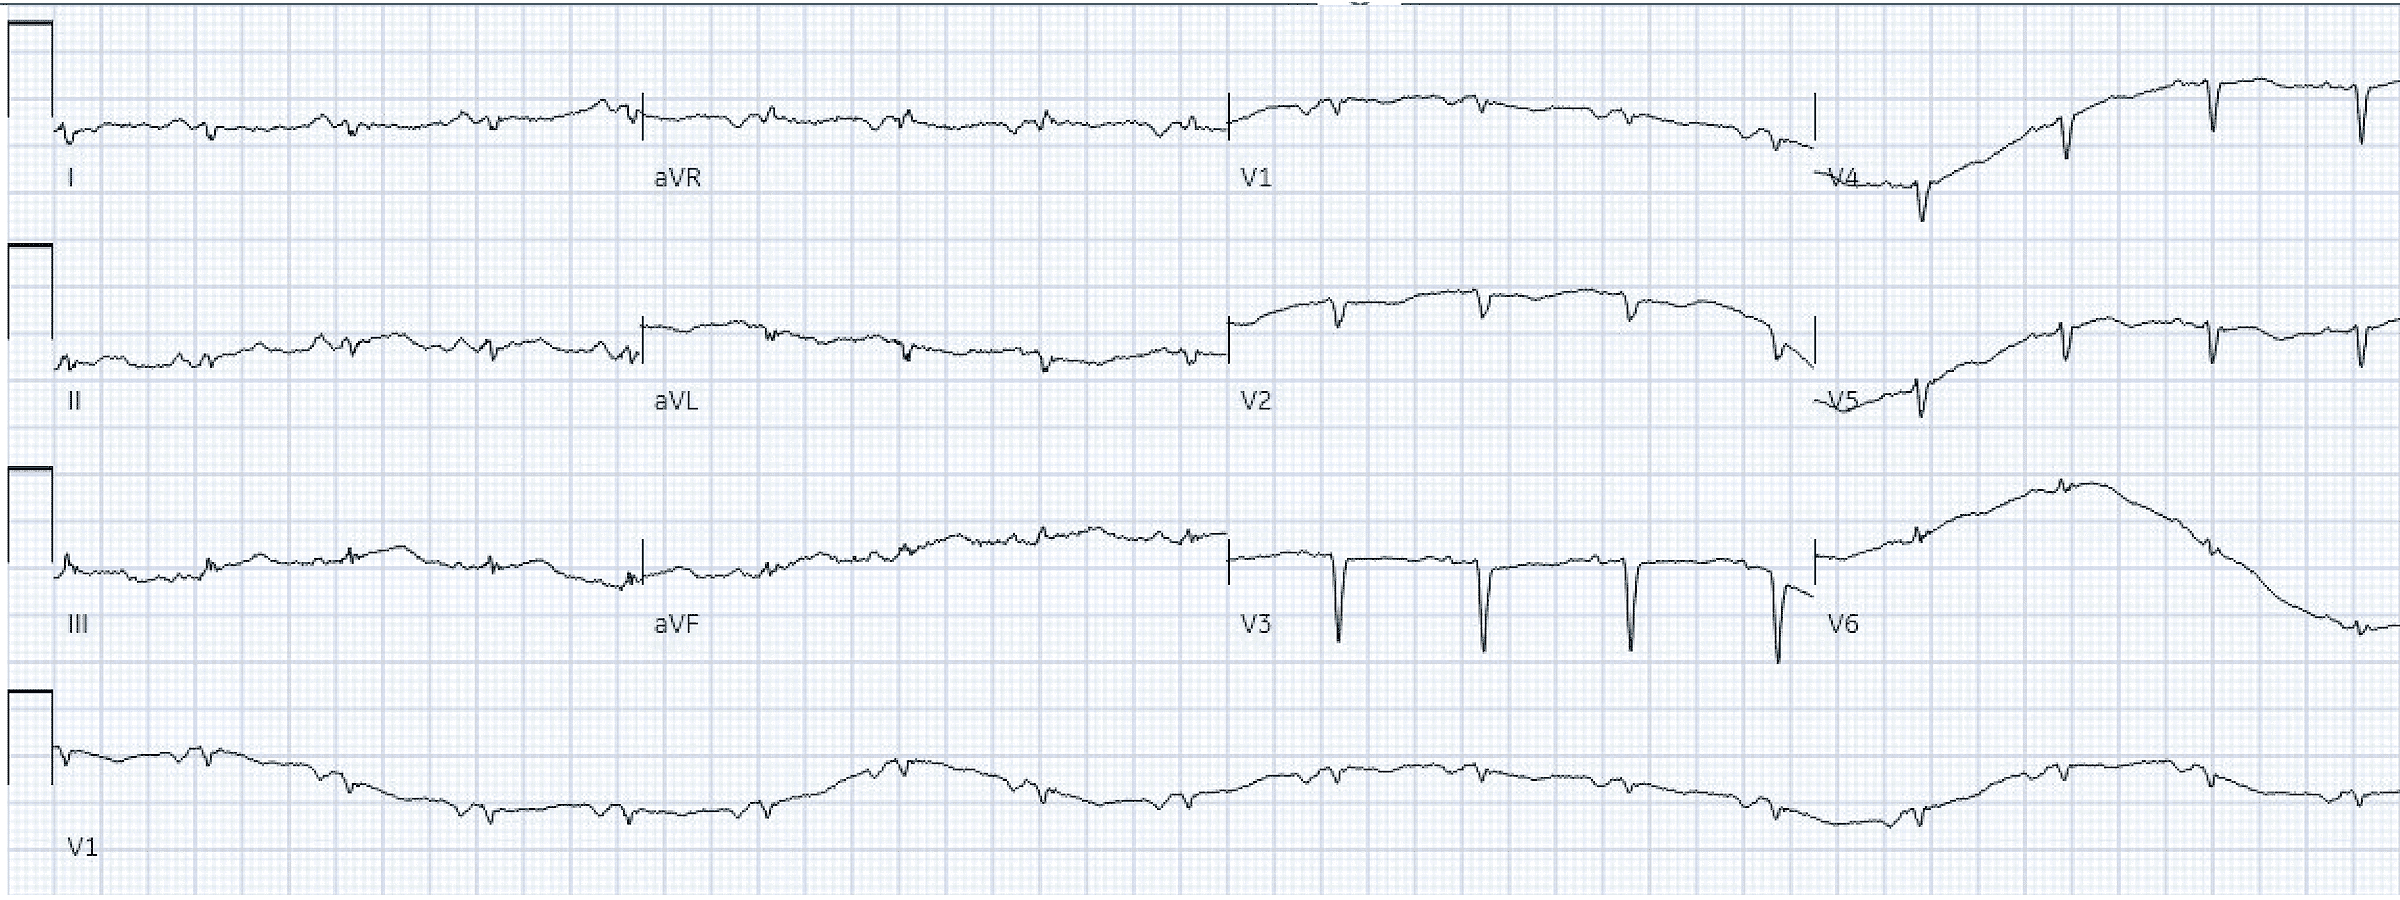

Пациент 40 лет с сахарным диабетом 1 типа и гиперлипидемией поступил в отделение неотложной помощи с гриппоподобным заболеванием в течение 5 дней. Он затруднялся описать симптомы, но жаловался на сильную слабость, тошноту, рвоту, головную боль и боль в груди. Он отрицал лихорадку, кашель, одышку и контакты с больными. Пациент описал боль в груди как сильную, давящую и не иррадиирующую. Она не усиливалась при нагрузке и не уменьшалась в покое. Пациент дрожал и «скорая» обнаружила у него выраженную гипогликемию. ЭКГ была записана вскоре после прибытия:

ЭКГ 1

На ЭКГ много артефактов, а амплитуда очень мала, что затрудняет интерпретацию. Мы можем видеть достаточно, чтобы понять, что ритм - синусовая тахикардия. Тахикардия необычна для ИМО, если только у пациента нет кардиогенного шока (или развивающейся левожелудочковой недостаточности). Отсутствие передних зубцов R предполагает передний ИМ неопределенной давности, но активного переднего ИМО не наблюдается.

Иногда, когда амплитуда настолько мала, а отношение сигнал/шум такое плохое, может быть трудно точно определить, как выглядит QRS, сегмент ST, зубец Т и т. д. Часто бывает полезно найти отведение, в котором детали очевидны, например, полоса ритма V1. Затем вы можете сравнить их, чтобы внести ясность. Это показано ниже с отведением V6. Вертикальные линии отмечают начало и конец QRS (четко различимые на полосе ритма и направлены вверх), а горизонтальная линия отмечает изоэлектрическую базовую линию.

Само по себе отведение V6 можно было бы и пропустить. Когда вы сравните его с V1, вы сразу же сможете оценить огромную площадь под кривой зубца Т V6, что указывает на острейший зубец Т. При осмотре соседних территорий, внезапно становится гораздо более подозрительным aVF и в меньшей степени отведение II. В целом это убедительно свидетельствует о нижне-боковом ИМО, особенно у пациента с острой болью в груди.